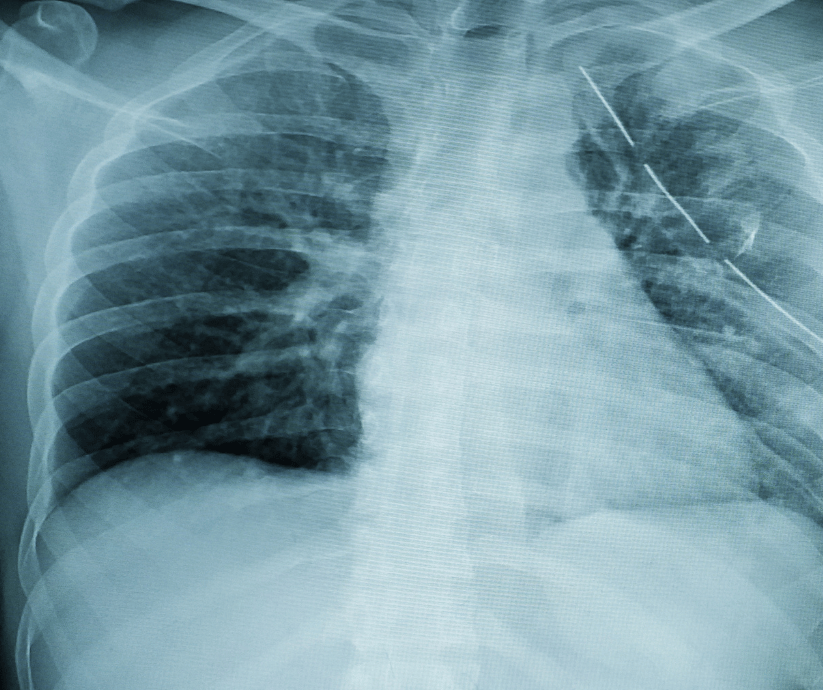

Proper documentation is critical in fracture injury claims. Immediate medical treatment helps establish the existence and severity of the injury. Medical records may include X-rays, CT scans, surgical reports, orthopedic evaluations, and physical therapy records. Following all treatment recommendations and attending follow-up appointments strengthens a claim. Personal documentation describing pain levels, mobility limitations, and daily challenges can further support medical evidence and demonstrate how the fracture affects everyday life.